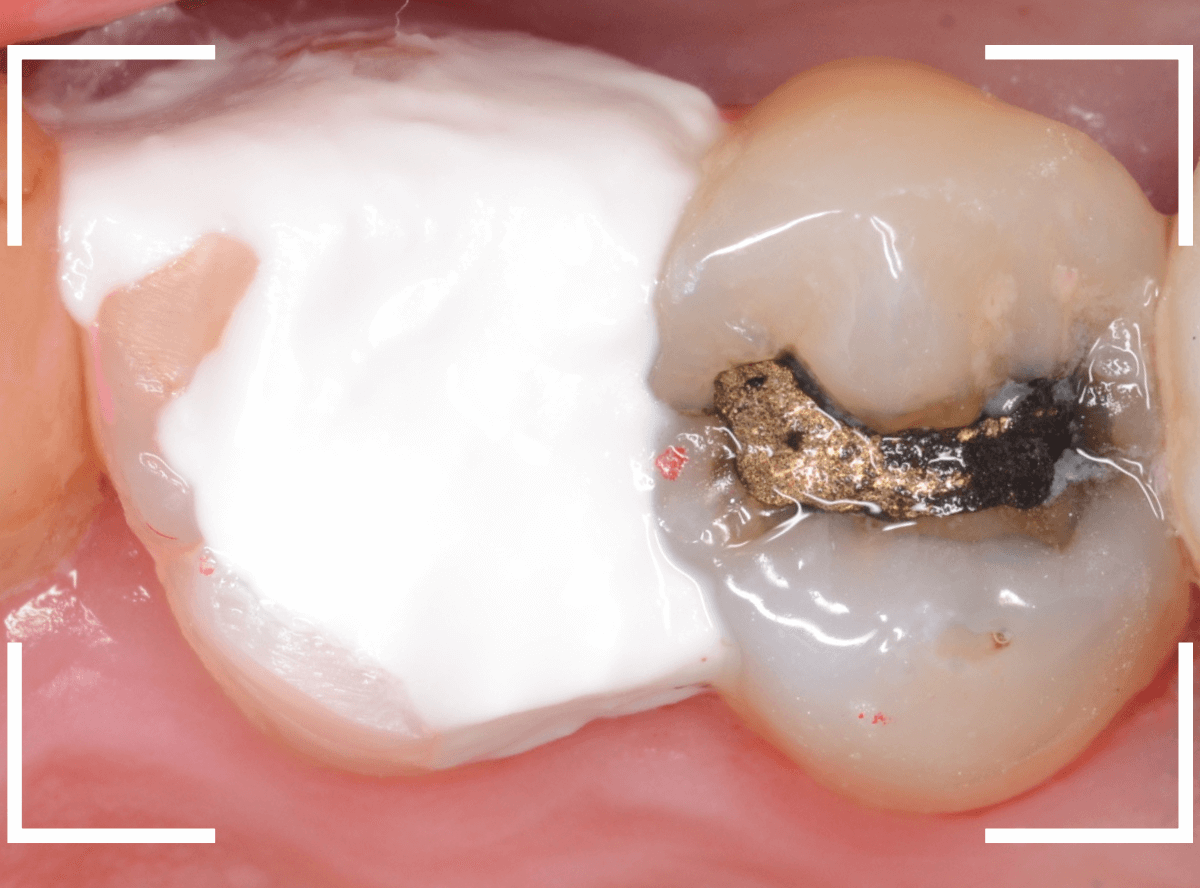

Case.15 歯の側面のレジンの中のわかりづらい虫歯

検診で、金属のつめ物のの中と、歯の側面に虫歯が見つかった方です。

まずは、手前(左)側の治療です。

こちらが、お口の中を見たところです。

〇部の中に虫歯があると思われます。

今回のように、金属のつめ物やレジン治療をしてある歯の側面の虫歯の診断はわかりづらく、難しいです。

金属のつめ物を外したところです。

この白いセメントの中に虫歯があると思われます。

セメントを除去したところです。

赤く染まっている部分が虫歯です。

真っ赤ですね(^^;)

まだ薄く染まっています。

もう少し除去する必要があります。

全ての虫歯が取れました、かなり深い神経まで近い虫歯でした。

金属のつめものをを外します。

つめものの下で虫歯になっていたせいで、虫歯と一緒に手前側のエナメル質がガリっと欠けてきました(><)

前の治療でつめたセメントを外しつつ、虫歯治療を行います。

写真ではわかりづらいですが、赤く染まった部分を中心に、虫歯がかなり広がっています。

虫歯を全て取り切ったところです。

神経スレスレの部分まで広がった虫歯で、最後は神経に触らないようにエキスカを使った、手探りでの虫歯治療になりました。